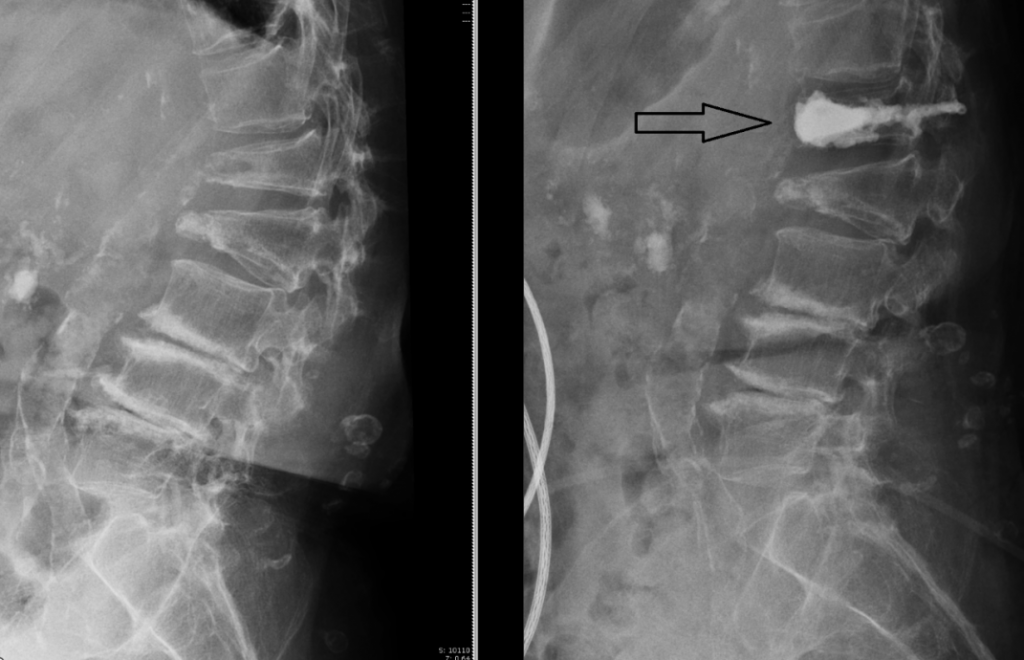

左图为微创水泥椎体成形手术(Cement vertebroplasty)前,右图箭头处为手术后。

正电子发射断层扫描(PET scan)显示L1塌陷。

在肿瘤科医生的建议下,陆妈妈来到我的诊所。她年纪不算太大,但却比同龄人更佝偻龙钟,由于背痛无法久站,所以女儿用轮椅推着她进来。我细看她们带过来的正电子发射断层扫描(Positron emission tomograhy, PET scan),发现造影图上只有腰椎崩塌处亮起高代谢信号,其他身体部位并没有亮信号,以我的经验来看,我推测陆妈妈很大可能纯粹是骨质疏松,造成腰椎崩塌,而不是癌症导致病理性骨折。

除了L1塌陷,我也在L2发现轻微塌陷的旧患。由于塌陷的腰椎没有压制神经中枢,的整体构造还相当稳定,所以我建议陆妈妈服食止痛药和肌肉松弛剂,并佩戴腰封,舒缓腰背疼痛,如果情况继续恶化,我才会为她进行微创水泥椎体成形手术(Cement vertebroplasty)。